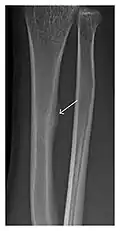

Figure 11: Stress fracture of the right radius in a 40-year-old man, a semiprofessional billiard player, with no history of trauma and complaining of pain of the right forearm for one month. (a) Anteroposterior radiograph shows medial radial cortex periosteal reaction (arrow) but no fracture line is seen. (b) Coronal reformatted CT depicts monocortical fracture line through the periosteal thickening (arrowheads). (c) Coronal T2-weighted fat-suppressed MRI shows intramedullary hyperintensity within the bone marrow (arrow) corresponding to bone marrow edema.[1]